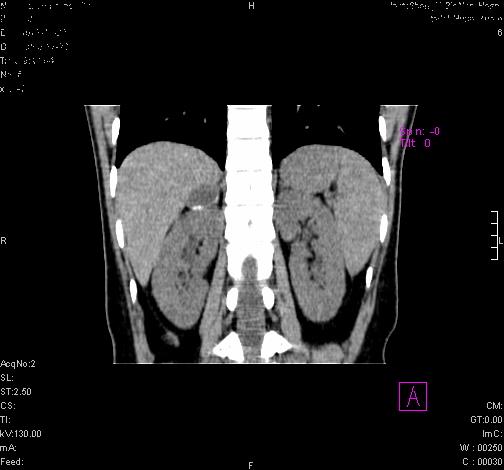

标题: CL0340:【】肾上腺囊肿,比较典型。

患者为年轻女性,查体发现右侧肾上腺囊性占位。无临床体征。

这么漂亮的图像,一看一目了然。典型的右侧肾上腺囊肿,周围有钙化。感谢搂主!

这么明显的弧形钙化,多考虑包虫病所致的寄生虫性囊肿。

右侧肾上腺囊性密度灶囊壁有钙化。考虑肾上腺囊肿,结核?